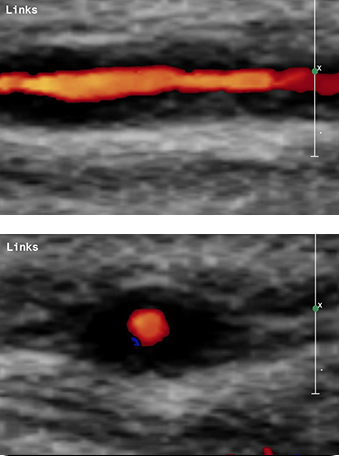

Aufgabe des behandelnden Arztes ist zum einen die Feststellung der Kopfschmerz-Ursache, hier kommt dem Ultraschall der hirnversorgenden Gefäße in der Hand des erfahrenen Untersuchers eine besondere Bedeutung zu, auch zur Frage nach Gefäßentzündung oder Gefäßverletzung. Zum anderen geht es um die Einleitung einer geeigneten Therapie, etwa bei Migräne oder Spannungskopfschmerz.